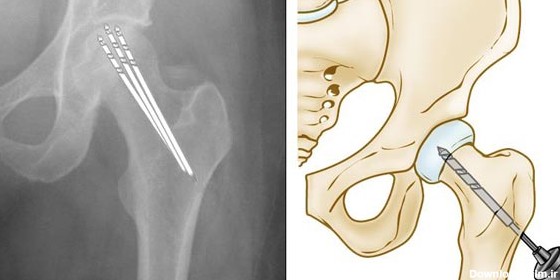

نکروز لگن یا سیاه شدن استخوان لگن و ران زمانی است که بافت استخوان به دلیل خونرسانی بسیار ضعیف میمیرد و می شکند و نهایتا فرو میریزد...

سیاه شدن سر استخوان ران (سیاه شدن سر استخوان ران)یا همان استئونکروز فمور (نکروز آواسکولر) که باعث درد لگن می شود و راه های درمانی و جراحی آن

سیاه شدن سر استخوان ران یکی از درمان های نکروز ، تعویض مفصل ران می باشد . بسیاری از افراد می پرسند چرا زمانی که تنها سراستخوان ران سیاه می شود